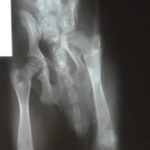

Layla has always had a bit of a limp and a turned out left hind leg. We had her x-rayed to see what was going on and we were shocked to see that the abuse she received by the kick fractured her pelvis and acetabulum and drove the head of her femur into the shattered socket. She has already developed some osteoarthritis and will have to undergo a femoral head osteotomy when she is a little older. With this surgery, she should be pain free and have no further complications from her injury. We will absorb the cost of this surgery if she finds a home here in Guatemala. It cannot be performed until she is a little older.